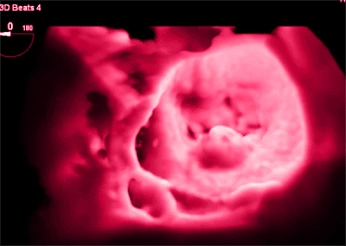

Ecocardiografia 3D

Permitindo análises volumétricas precisas e novas métricas de função.